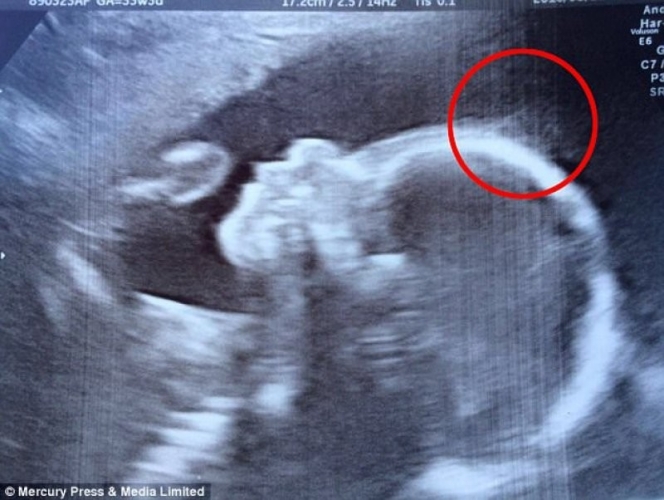

28 жастағы британиялық Наташа Гент жүктіліктің жиырмасыншы аптасында ултьрадыбысты тексеруден өткен. Болашақ ана тексеру барысында ерекше сұлбаны байқайды. Дәрігерлердің көмегімен ерекшеліктің не екені анықталды. Анасының ай-күні жеткенде сәби "шашпен" дүниеге келген, деп хабарлайды Қамшы ақпараттық агенттігі.

Босанғаннан соң сәбиді көрген анасы таң-тамаша күйге бөленген.

Сәбидің шашпен дүниеге келуінің өзі бір тылсым күш екені анық. Төменде қалың әрі ұзын шашты 4 айлық сәбидің суреті.